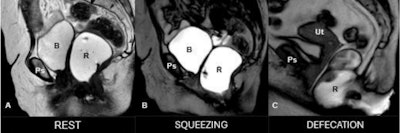

Real-time evaluation of PFD Using T2-weighted interactive single shot sequence (SSFSE) in dynamic MR defecography. Dynamic MR defecography using T2-weighted SSFSE sequence shows pelvic floor anatomy at rest (A), during squeezing (B), and defecation (C). Progressive descent of pelvic organs suggests pelvic floor dysfunction. B: bladder, Ps = pubic symphysis, R: rectum, Ut: Uterus.Pugliesi et al; EJR